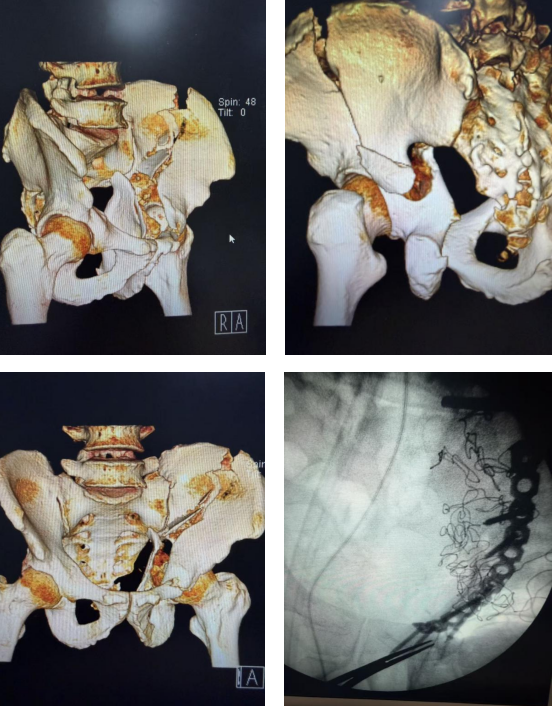

从“破碎”到“完整”:苏高医骨科助力200余斤复杂髋臼双柱粉碎性骨折患者康复

近日,苏州高新区人民医院骨科成功为一名体重达200余斤的复杂髋臼双柱粉碎性骨折患者精准实施复位内固定手术。 面对患者超常体重与复杂骨折的双重挑战,骨科团队在多学科协作下以精湛的技术顺利完成该手术。目前,患者恢复良好。

创伤骨科王玉方主任介绍,髋臼是连接躯干与下肢的“承重之桥”,其骨折因解剖位置深、毗邻重要神经血管、复位固定要求高,历来是骨科创伤治疗的难点。此次收治的患者因车祸导致髋臼前柱与后柱粉碎性骨折——这意味着其髋关节的“碗状”结构已完全碎裂、移位。更为棘手的是,患者体重达200余斤,厚重的软组织层给手术视野带来极大困难,术后骨骼需承受的超常负重,对内固定物的力学强度提出严苛要求;同时,因患者体重偏大也显著增加了深静脉血栓、感染等并发症风险。

面对挑战,骨科团队进行了详细的术前评估,决定采用经典的髋腹股沟入路。术中,由贾鹏主任医师主刀,将粉碎的骨块逐一精准复位。复位完成后,团队采用特制钢板与螺钉系统进行坚固内固定,为碎裂的骨骼搭建起足以支撑早期康复锻炼的“内部脚手架”。整台手术出血量极少,且有效保护了神经。

术后在大骨科刘勇主任的指导下,骨科联合康复科为患者量身定制分阶段康复计划:从早期踝泵运动预防血栓,到不负重关节活动度训练,每一个环节都在专业指导下科学推进。目前,患者恢复良好。